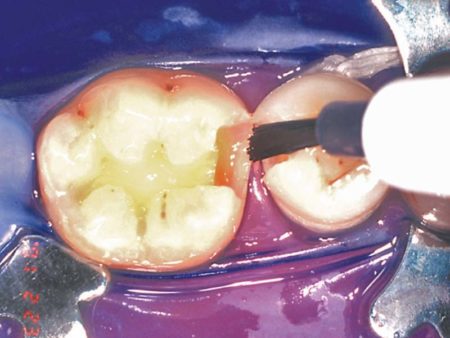

Fig. 3: Use DenTASTIC™ UNO™ for light cure, or UNO + DUO for self-cure or dual cure applications

Fig. 4: Light cure for only 10 seconds

Photos courtesy of Dr. C. H. Pameijer